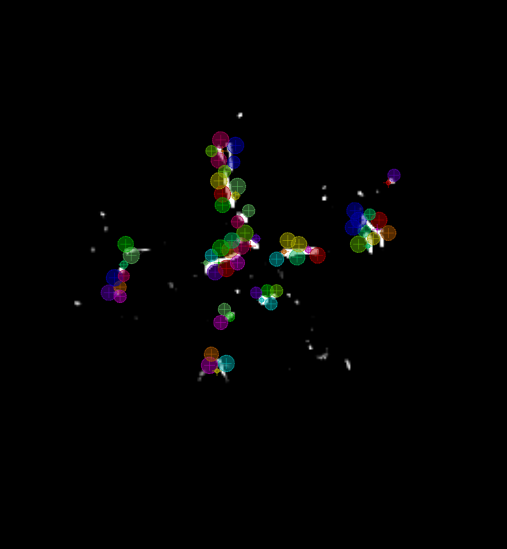

Figure 4: VirtualDSA++ model showing the ICA, MCA and ACA together with the placed markers. Highlighted in green is a path computed by the path search algorithm.

Refer to caption

Figure 5: VirtualDSA++ model of the Circle of Willis, the ICA, MCA and ACA together with their transformed marker chains.

4.2.3 Path Search

Proper path planning is crucial when planning mechanical thrombectomy, i.e. the physical removal of the blood clot causing the ischemia. Often, the catheter enters the intracranial system via the ICA to remove clots in it or in the MCA. The latter case is shown in Fig. 4.2.3, where the root marker is displayed as a blue cube on the bottom right. In green the shortest path from the ICA root to the MCA is visualized. As the path search has been done and all properties are determined for all nodes, arbitrary shortest paths with respect to the root node can be visualized interactively in real-time. The path search can be used to readily annotate vessel segments for the purpose of documenting the findings, e.g. for reporting.